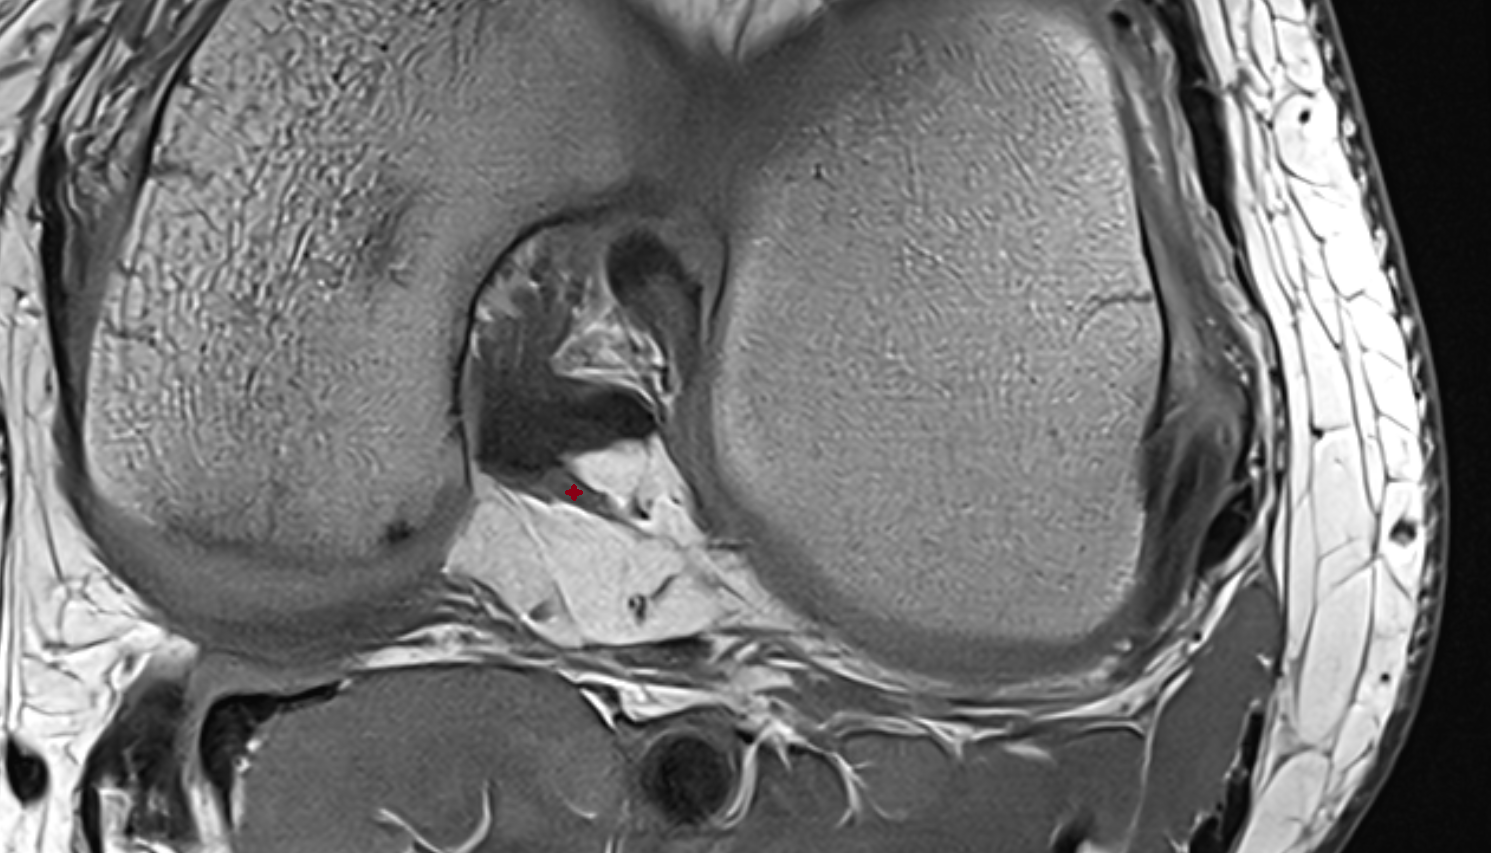

- Anterior cruciate ligament

- Posterior cruciate ligament

- Medial meniscus

- Lateral meniscus

- Knee Joint